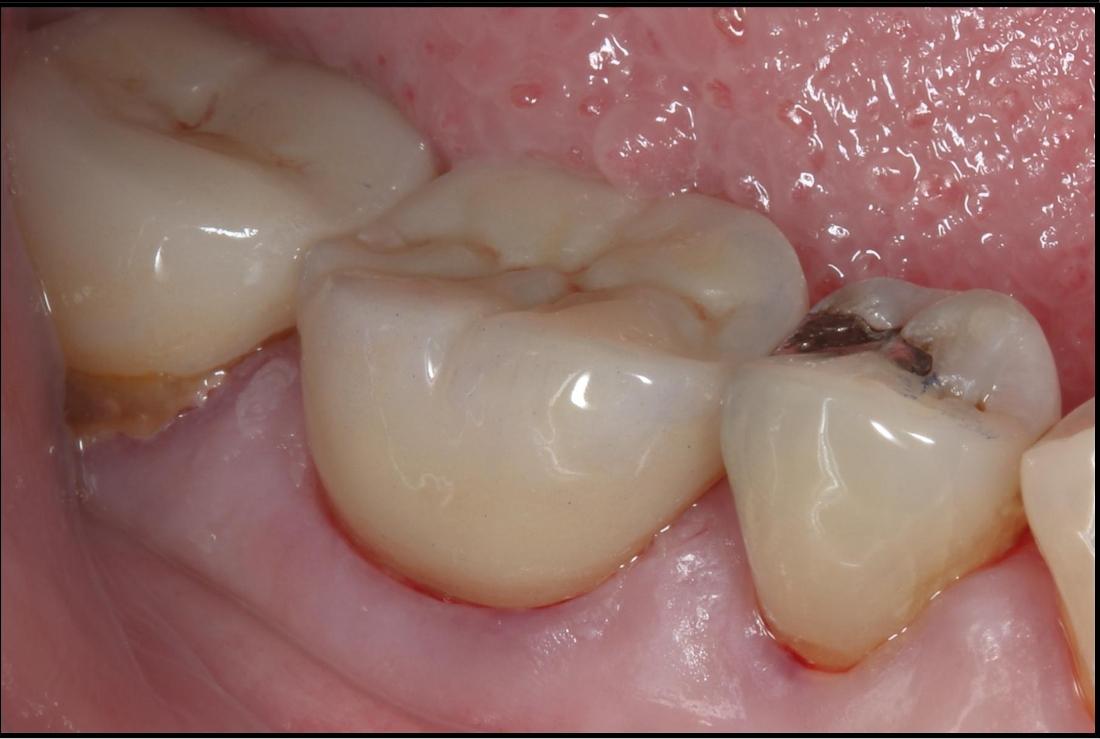

Large amalgam fillings very often lead to the fracturing of teeth over time. This tooth had a large amalgam filling which had begun to leak, allowing bacteria to enter and cause decay. It also had a fractured cusp and several other developing fractures. If left untreated, further breakdown would have lead to toothache and possibly the need for extraction. Here a crown was placed, giving it a new hard wearing outer shell that will prolong the life of this tooth.